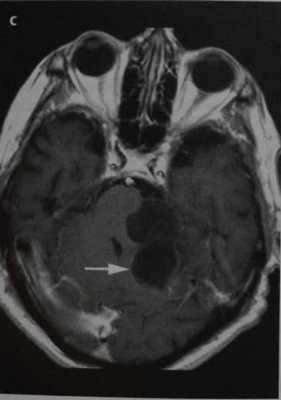

МРТ головного мозга. Т1-взвешенные корональная и сагиттальная МРТ. Эпидермоидная киста левой височной доли.